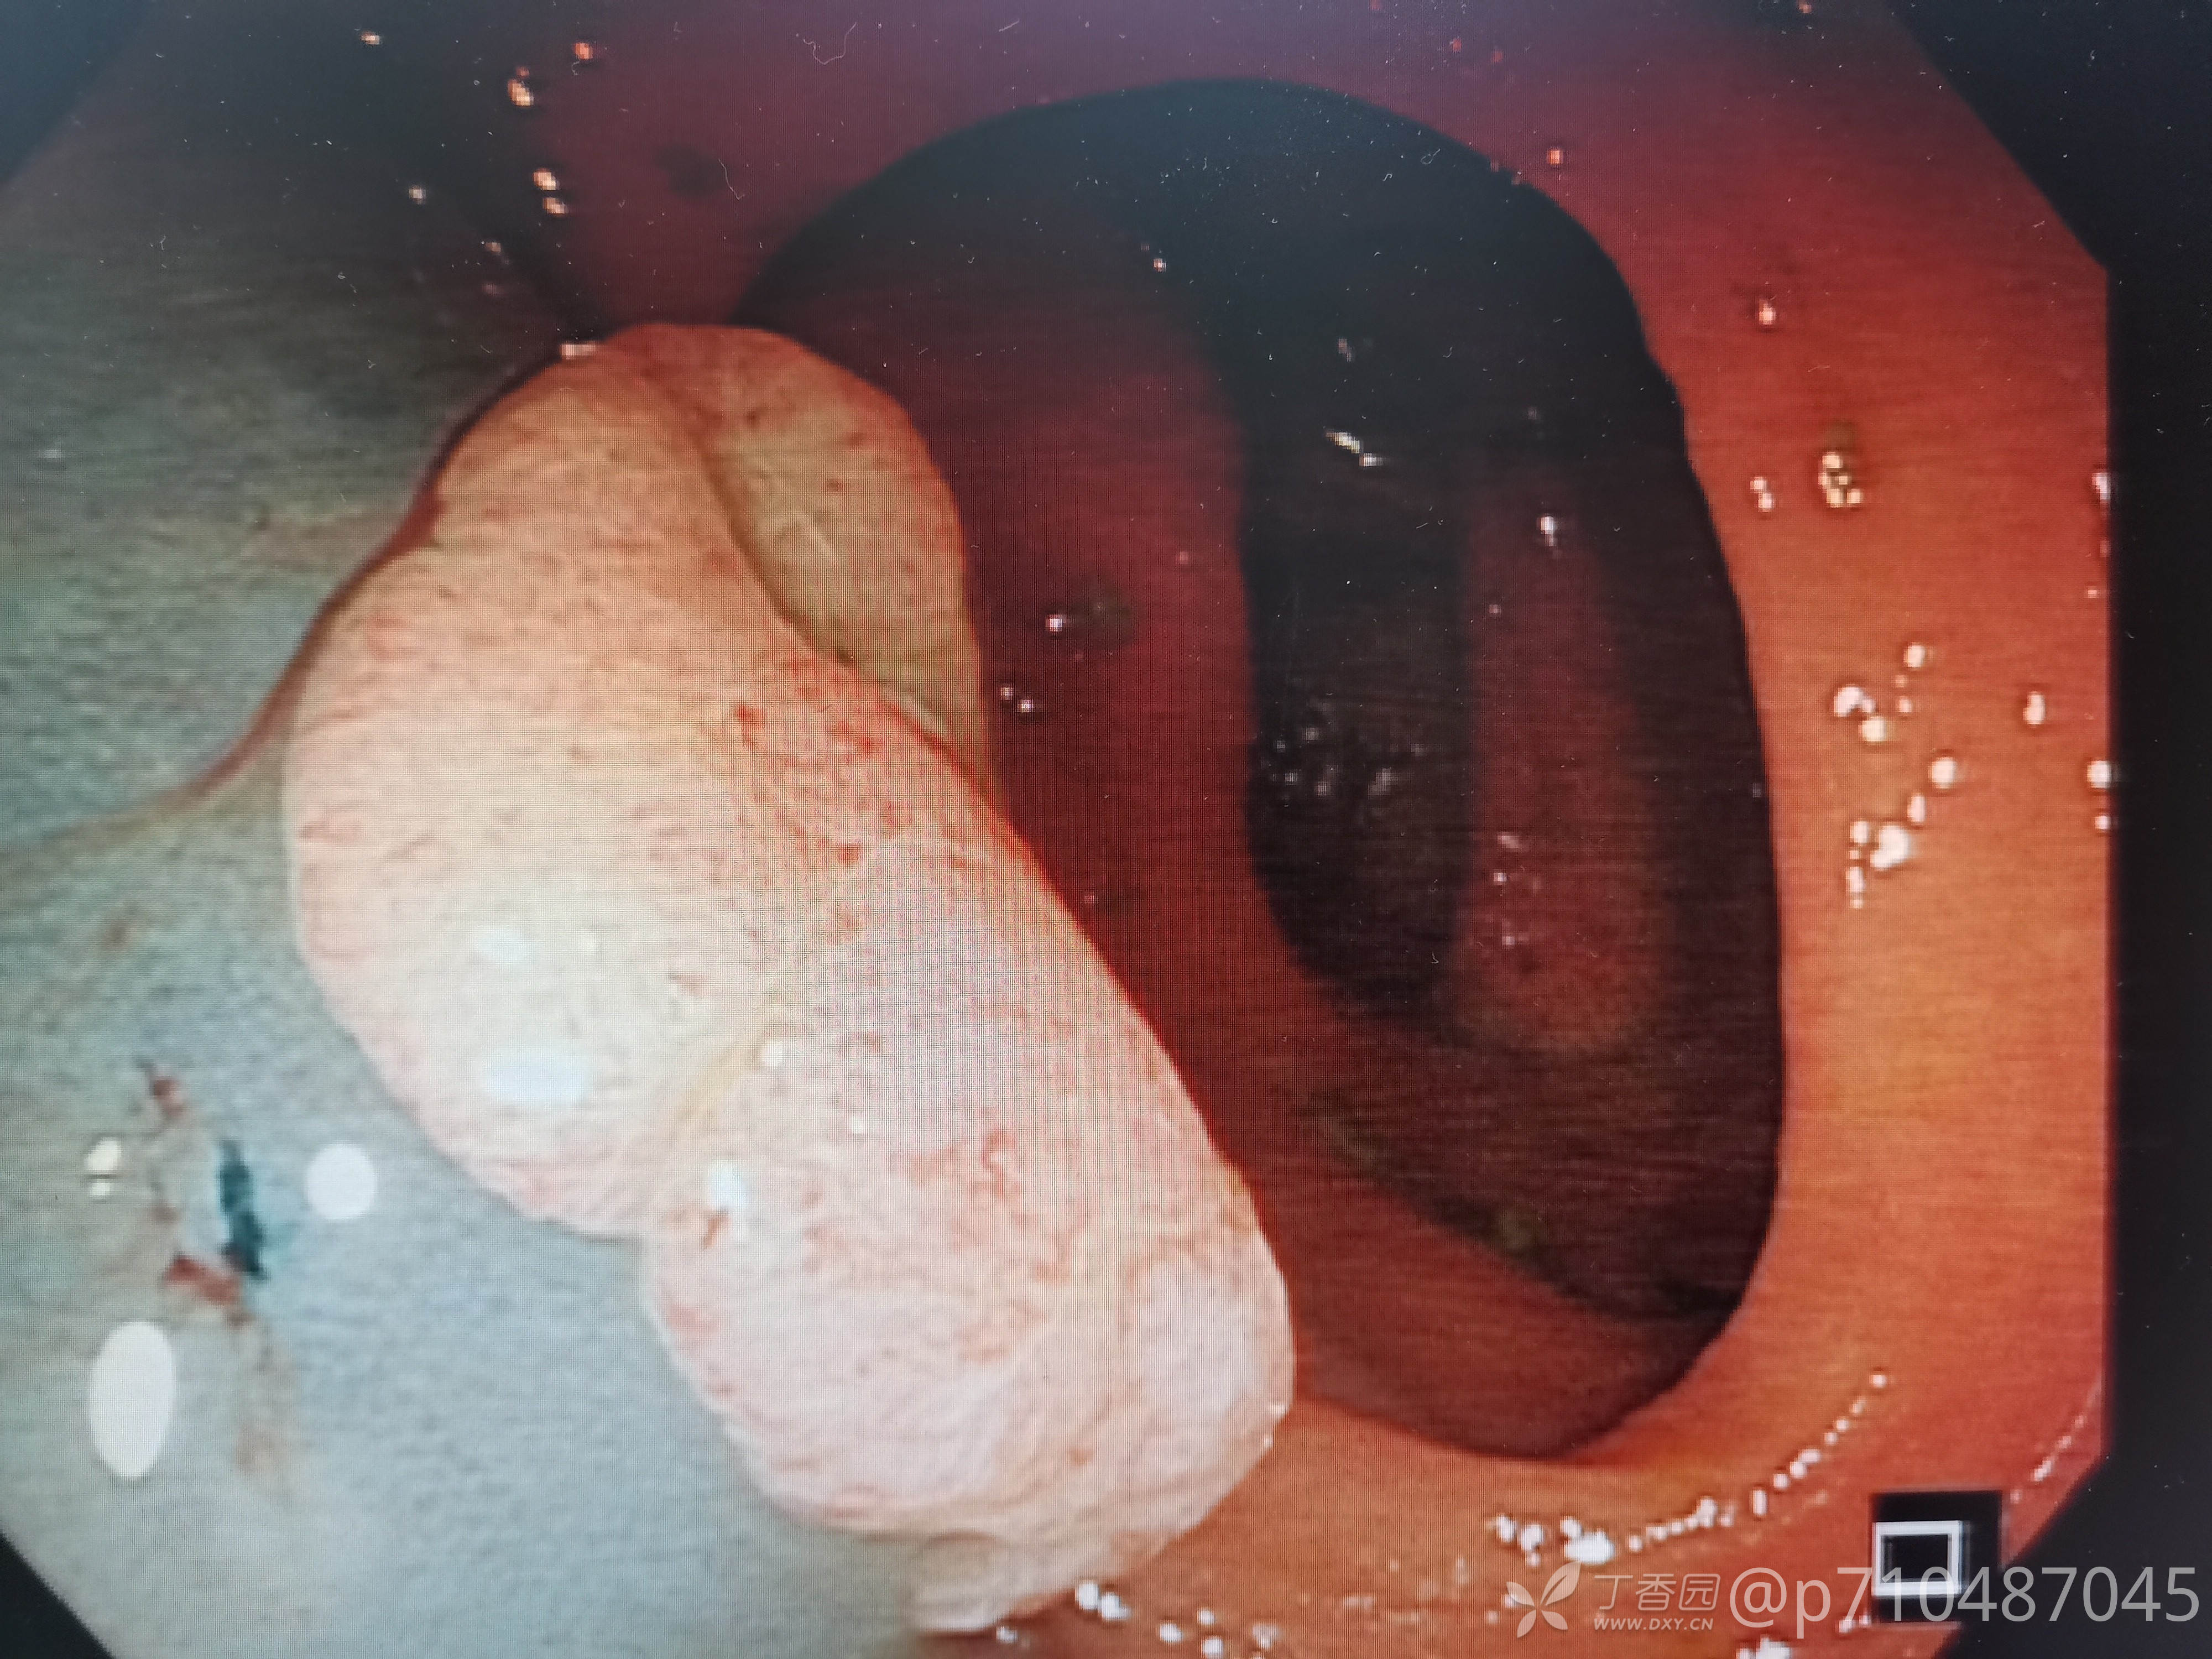

西兰花饺子 推荐第一例病人男性,50岁,第一次行肠镜检查,发现大小息肉5颗,较大者予EMR切除,这么大的第一次切,感觉可以做ESD了😂最后一个夹子打的有点松😳,来回进出几次没发现活动行出血才敢继续退镜。